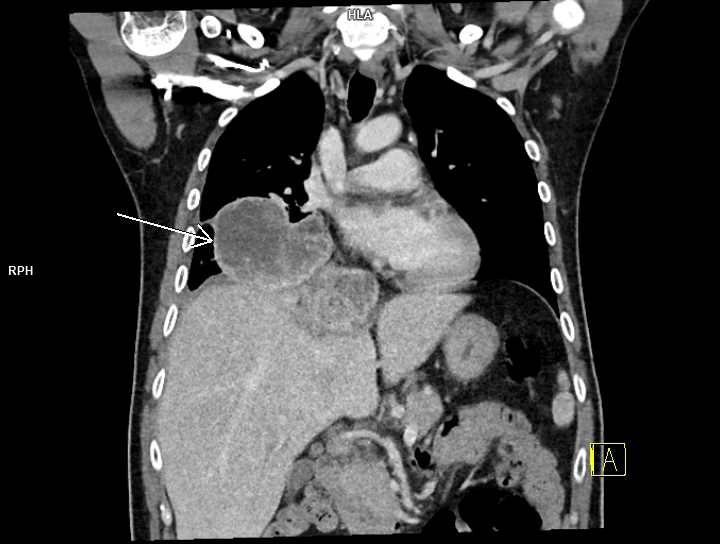

Figura 3: coronal CT în timp venos torace și abdomen

Discuţie caz nr 99: pacientul s-a prezentat în urgență și a fost trimis la examinarea CT cu suspiciune de trombembolism pulmonar. Examinarea CT efectuată toracic care a surprins și o parte din abdomenul superior evidențiază trombembolism pulmonar acut stâng la nivelul arterei intermediare cu evoluție și la nivelul arterelor segmentare și subsegmentare precum și tumoră renală stânga de pol inferior cu aspect de carcinom cu celule clare (Grawitz) și determinări secundare pleurale drepte.